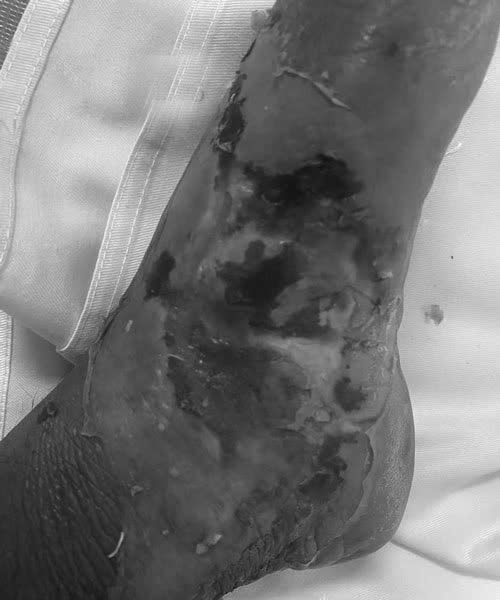

Người đàn ông nhiễm trùng nặng vì tự ý đắp thuốc sau khi bị rắn cắn

Sau khi bị rắn cắn vào cổ chân, người đàn ông tự điều trị bằng thuốc nam tại nhà dẫn tới hoại tử, nhiễm trùng nặng.